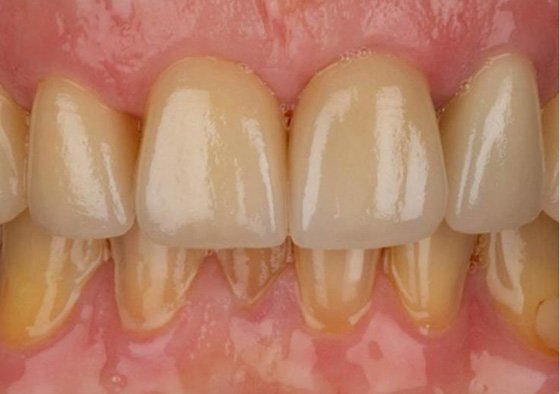

Final restorations showing 3M™ Lava™ Esthetic Fluorescent Full-Contour Zirconia crowns with desired incisal translucency.

Final restorations with esthetic zirconia crowns

FINAL RESULTS: Zirconia restorations in place one week after cementation. Patient was very happy with the final appearance of his seated final restorations; no post-op sensitivities were reported after final cementation.

Results of zirconia restorations